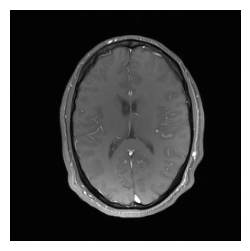

Now, we have an image which is 256 x 256 voxel as we would expect. Let’s combine the data from the different receiver coils using root-sum-of-squares and then display the image. Note that we usually index from behind in MRtwo (i.e. -1 for the last, -4 for the fourth last (coil) dimension) to allow for more than one ‘other’ dimension.

# Combine data from different coils and show magnitude image

magnitude_fully_sampled = img.abs().square().sum(dim=-4).sqrt().squeeze()

show_images(magnitude_fully_sampled)